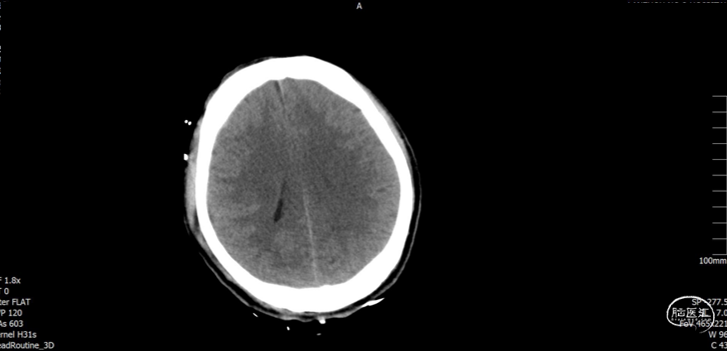

术后随访

术后72h CT,复查后拔除硬膜下引流管

术后72h胸部 CT

术后1周 CT

术后70天CT